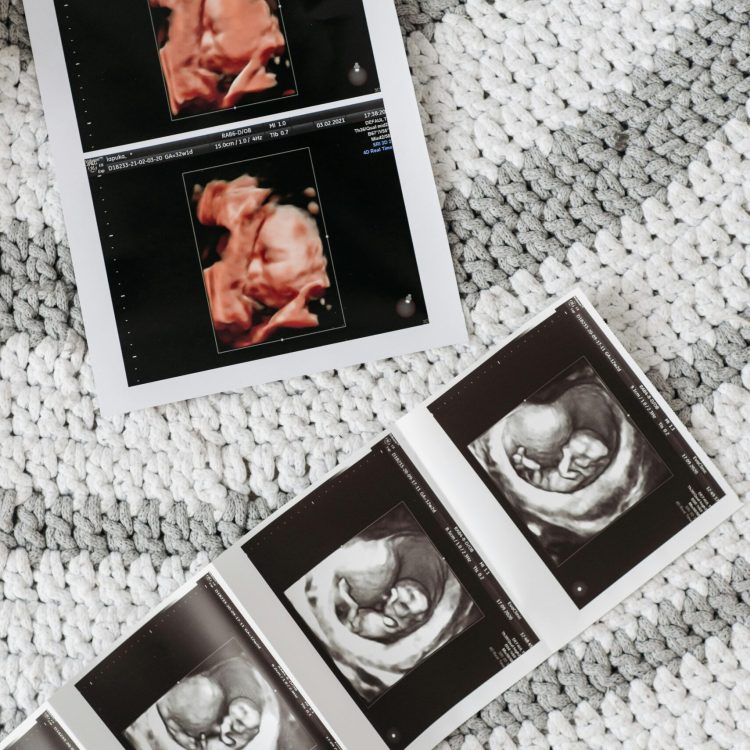

Ultrasound photos of a baby | How often do I need to get an ultrasound | Mary's Refuge, Martinsburg WV

An ultrasound is an exciting part of pregnancy, offering a glimpse of your growing baby and providing important medical information. The number of ultrasounds you’ll need depends on various factors, including your healthcare provider’s recommendations, your medical history, and how your pregnancy is progressing.